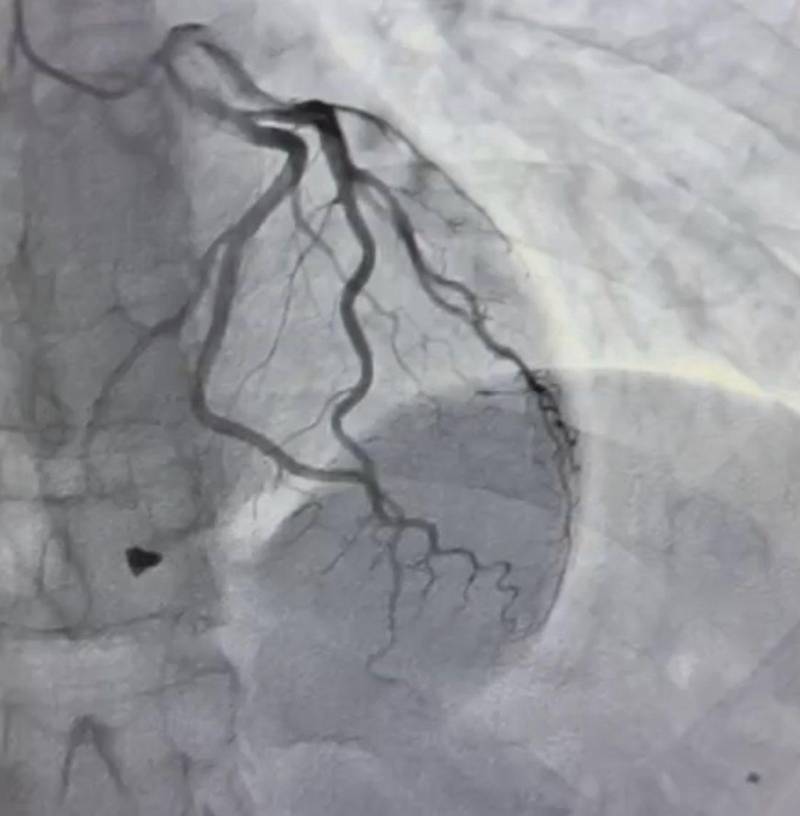

“Під час ретельного обстеження пацієнта встановлено: металевий уламок локалізувався в зоні клапанного апарату серця з пошкодженням папілярного мʼяза тристулкового клапана. Це не просто травма, а загроза втрати повноцінної та компетентної роботи клапана серця. Після детального аналізу анатомії травми кардіохірургічною командою лікарні виконано видалення вогнепального осколка та пластику тристулкового клапана, що дозволило відновити його функцію і забезпечити стабільну роботу серця”, – йдеться у повідомленні.